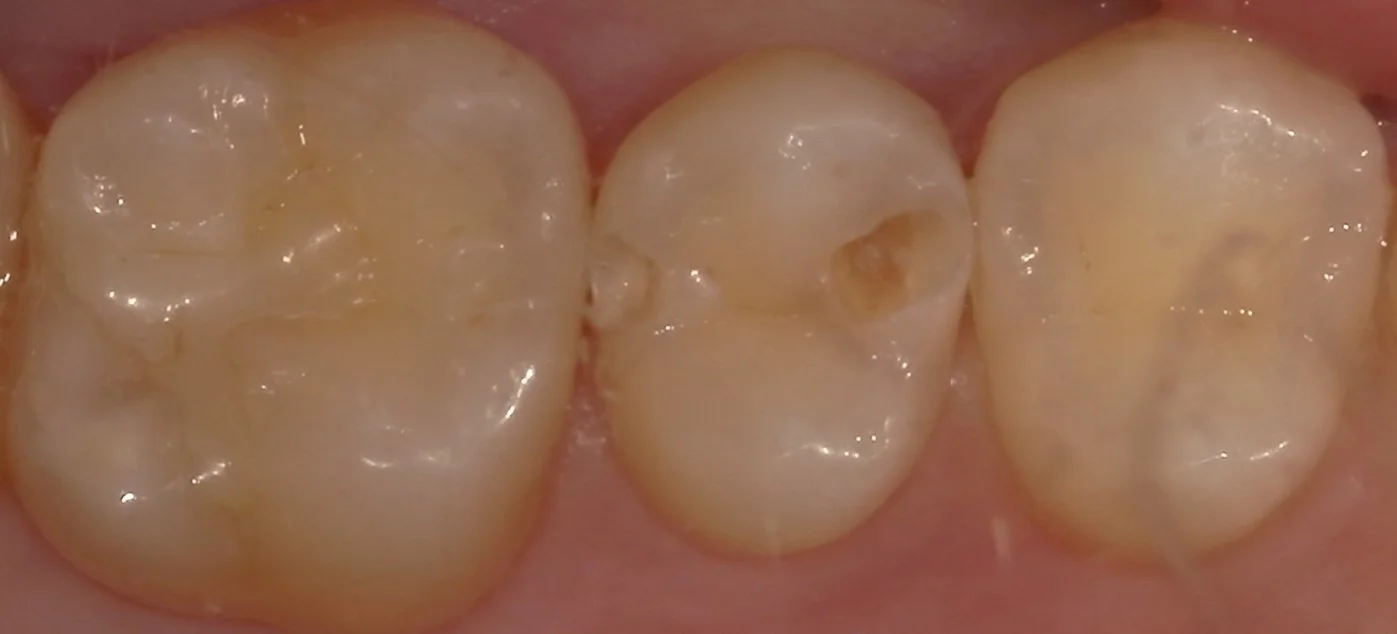

歯を軽く削って虫歯を露出させたのがこちらです。

これで見ても、黒くないので虫歯はそんなに大きくないように見えるかもしれませんが・・・

実は黒い虫歯は慢性う蝕と言って進行が緩慢なのに対して、こういう風に色素の薄い虫歯は急性う蝕と言って、進行が急速であることが多いです。